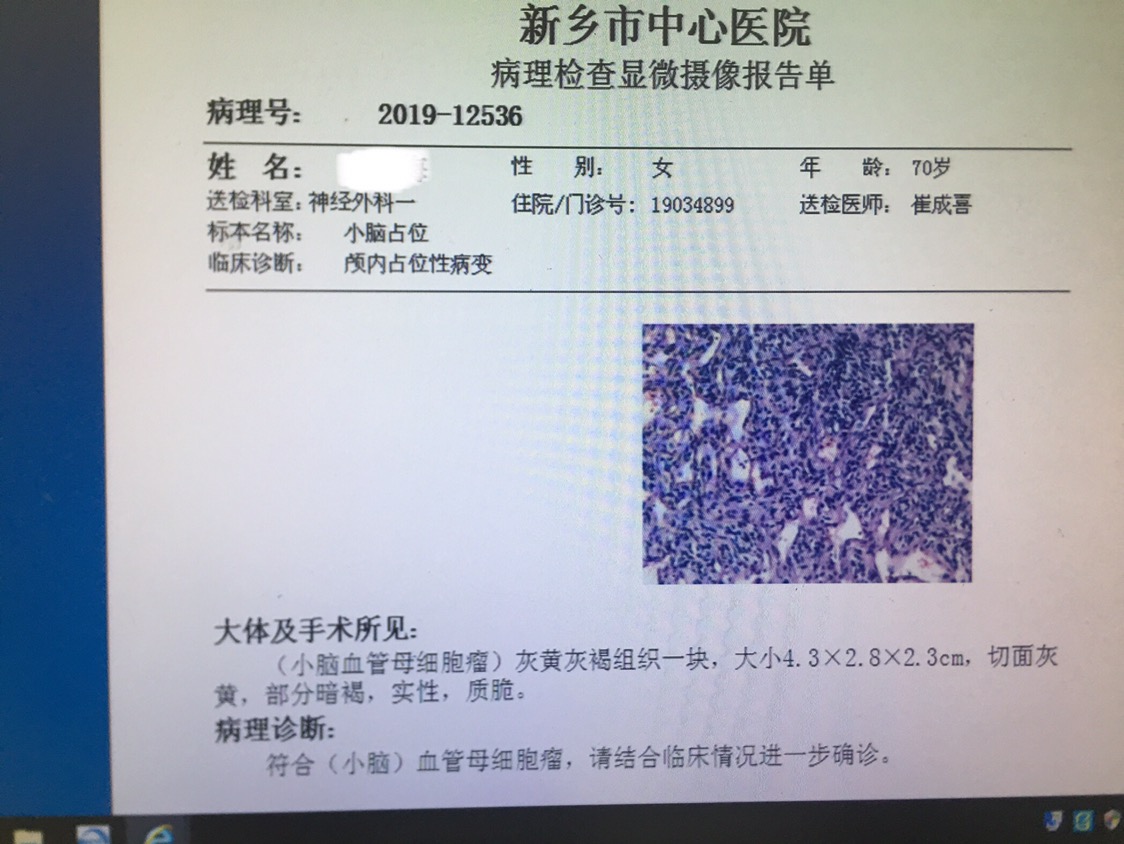

患者周某,女,70岁,以“间断头痛伴恶心呕吐五天”为主诉入院。既往患有高血压病3年,糖尿病3年,冠心病2年,控制情况一般。查体:神志模糊,精神差,可对答,回答正确,能完成简单指令性动作,反应迟钝,双瞳孔等大等圆,直径约3mm,光反射灵敏。指鼻试验不准,轮替试验缓慢。跟膝胫试验不稳。病理反射未引出。诊断:1.左侧小脑实性血管母细胞瘤,2.梗阻性脑积水,3.高血压病,4.冠心病,5.2型糖尿病。

增强轴位

增强冠位